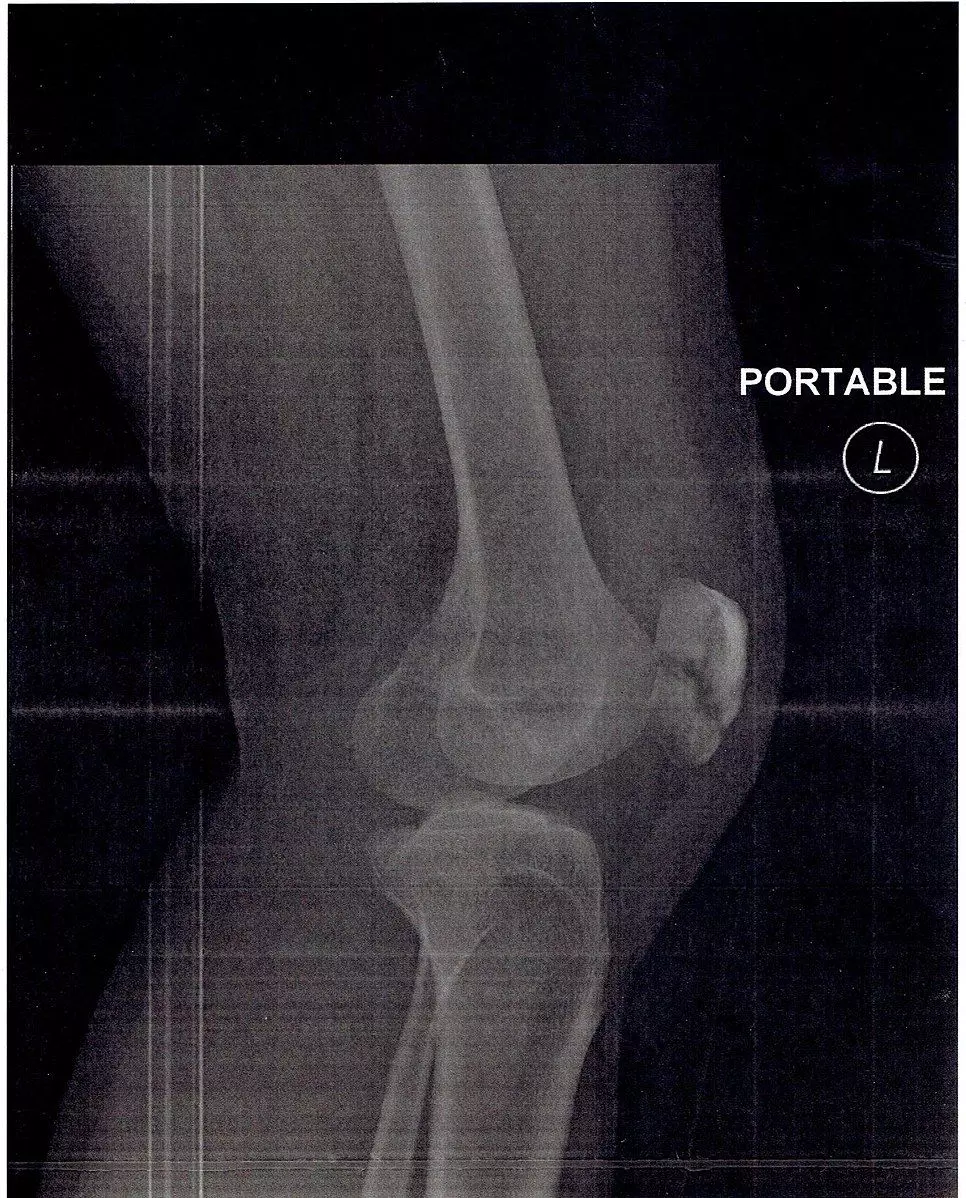

Fractures of the patella are often caused by direct impact or indirect eccentric (not central) contraction of the quadriceps (contraction to straighten the leg when the knee is not straight below the hip but deviated to the side). They are most commonly seen in 20-50 year olds and usually present with: swelling (due to bleeding at the site of fracture), a palpable defect and an inability to perform a straight leg raise (if patella fracture is displaced).

Treatment of a non-displaced patella fracture is to use a long leg cast or knee immobiliser to allow the patella to remain in the correct position while it heals. If the patella fracture is displaced, surgery is the most likely option for treatment. In both cases physiotherapy may be required to return the leg to full function, once it can bear weight again.

It is important to bear in mind that a bipartite patella can be a normal finding, particularly in adolescents. In a young person presenting with a patella in two parts on imaging, this does not always represent an acute fracture, and management should be guided by the clinical history and examination.

Image - An X-ray of a patella fracture

Creative commons source by Carlo Joseph Moskito [CC BY-SA 4.0 (https://creativecommons.org/licenses/by-sa/4.0)]